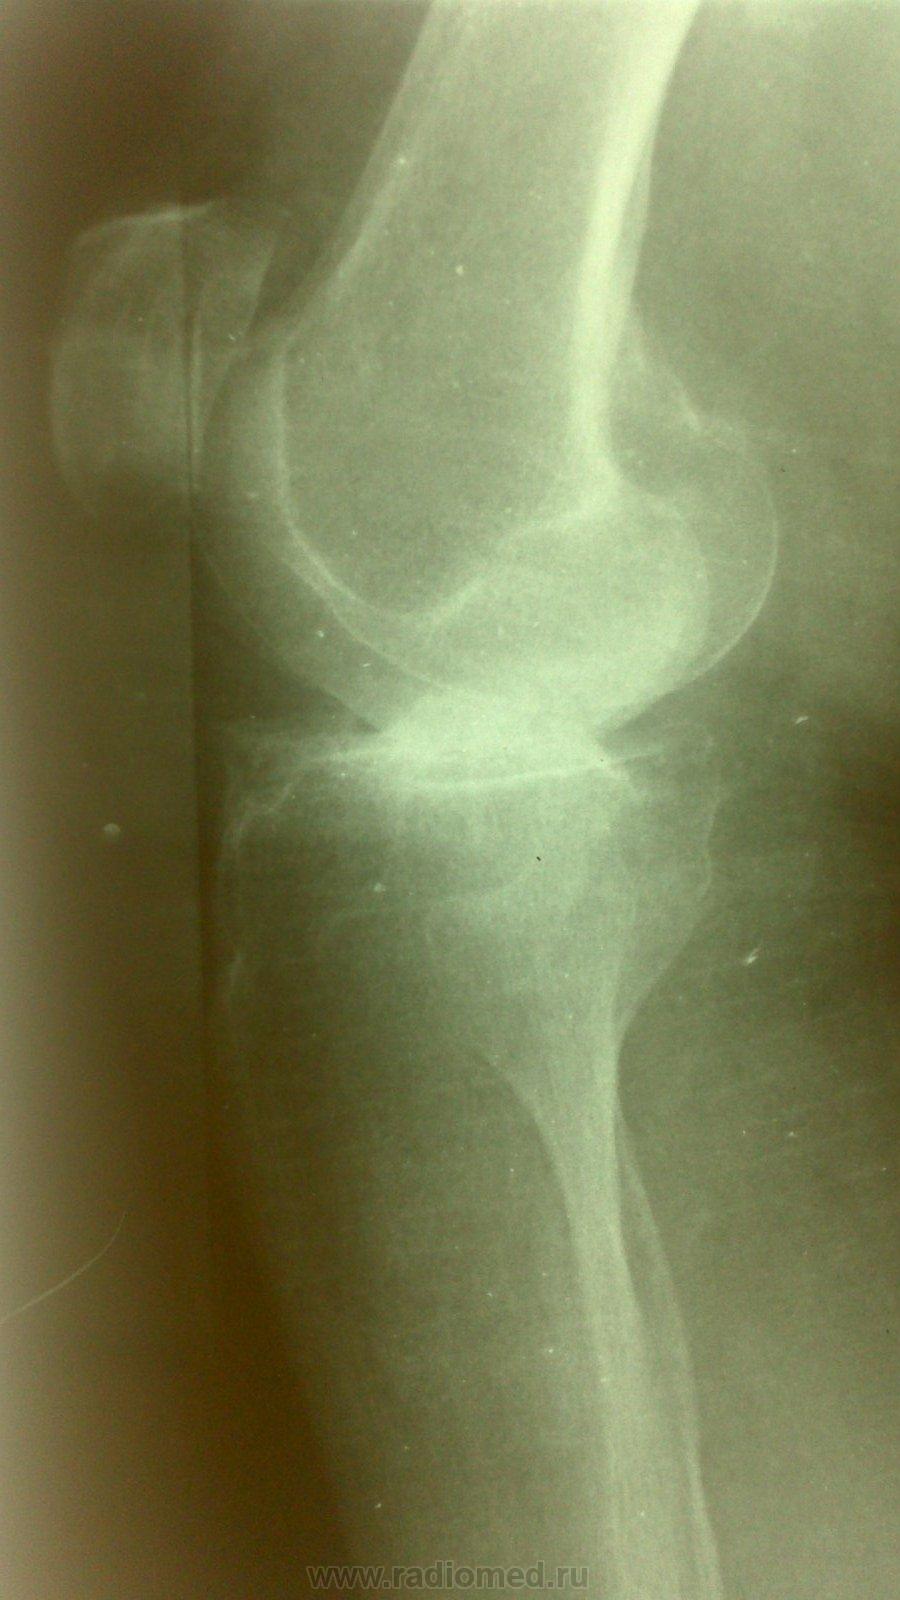

Бабушка 75 лет. Жалобы на боли в суставе. Предыдущих снимков не предоставлено. Со слов на них артроз. На снимках правого сустава Р пр-ки артроза 1 ст.

Значительное сужение суставной щели в наружнем отделе,контактный склероз. Подвывих?

Как с движениями в суставе? Артроз 3 стадии, подвывих. Возможно, боковые связки повреждены.

+ yes Вот хирурги вечно пишут "ДОА" при любых жалобах на боли в суставе. Так ВОТ - плиз:  оно и есть классик-  Деформирующий Остео-Артроз.

Коллеги, если с латеральным мыщелком бедра всё нормально,  по каким признакам артроз 3 ст. - кому авторство этого артроза присуждаете?

Может быть рассекающий остеохондрит(суставная мышь в латеральных отделах) в сочетании с гонартрозом

Мысль про асептический некроз мыщелка бедра посещала меня, но на боковой проекции совсем ровный контур обоих мыщелков, хотя и нечёткий - "мешают" межмыщелковые бугорки. Может, прямую проекцию всё-таки повторим... в должной укладке и без поворотов?)

Спасибо большое за участие. Выяснила,что в анамнезе была травма 10 лет назад с тех пор и беспокоит, в амбулаторной карте ни слова об этом. Посттравматический артроз?

Посттравматический артроз, думаю, и без нас поставят. Мне самому интересно - где та тень, которая на боковом немного... пропала. А Вам не интересно? Повторили бы снимок - развеяли бы сомнения, доказали бы заблуждения...